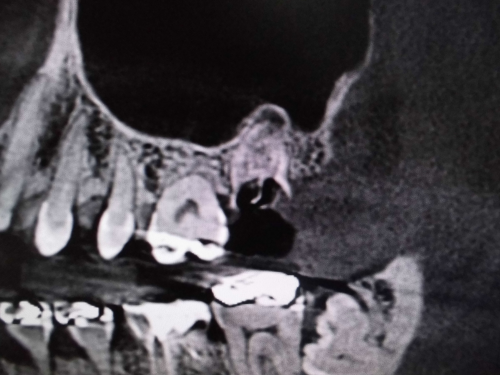

左上奥歯が割れています。一般的なレントゲンではわかりません。

CTでは破折線がはっきり見えます。患者様も納得しやすいです。

レントゲンでは不明な根尖病巣がCTでははっきり写ります。

同じ患者様です。根管が樋状根になっているのもわかります。

上顎洞との位置関係が確認できます。

原因が頬側近心根とわかりました。上顎洞粘膜が肥厚しているのもわかります。